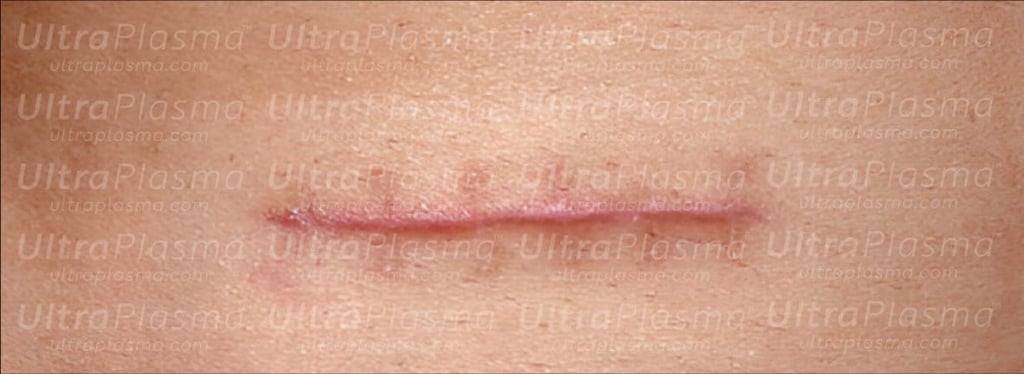

Scarring, a complex biological response to dermal injury, manifests in various forms including surgical, hypertrophic, keloid, atrophic, stretch marks (striae), and umbilical scars. Traditional treatments often fall short due to the variability in scar biology and patient response. UltraPlasma™, a next-generation dermatological technology integrating arc, argon, and helium plasma modalities, offers a multi-depth, multi-function strategy. This article explores the anatomical, biological, and engineering principles behind scar remediation using UltraPlasma™, including the effects on skin layers, reactive species interactions, and clinical applications.

Scars can result from trauma, surgery, acne, burns, or infections. Classified as:

Hypertrophic scars (confined, raised fibrous tissue)

5.1 Surgical & Hypertrophic Scars

Arc + Argon combo to reduce raised tissues and normalize pigment.

NO and O₃-mediated ECM restructuring and angiogenesis.